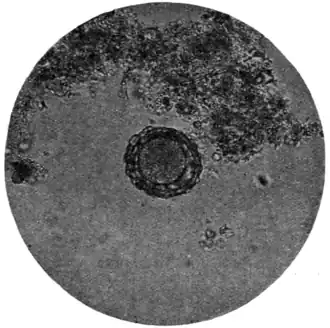

The ova of Ascaris lumbricoides (Fig. 168, f, g, and Fig. 171) are considerably larger (60 to 75 μ by 40 to 58 μ) than those of trichiuris (Fig. 168, c). They are also, as a rule, more spherical, or rather, more broadly oval; occasionally they are almost barrel-shaped. Like those of trichocephalus, they are dark brown in colour from bile-staining, but they are much less sharply and smoothly defined, possessing a coarse thick shell which is roughened by many warty excrescences. The yolk contents are not always easily made out, nor, when made out, can any sign of embryo or segmentation be discovered.

Fig. 171.—Ovum of A. lumbricoides, x 250. (Photograph by Dr. J. Bell.)